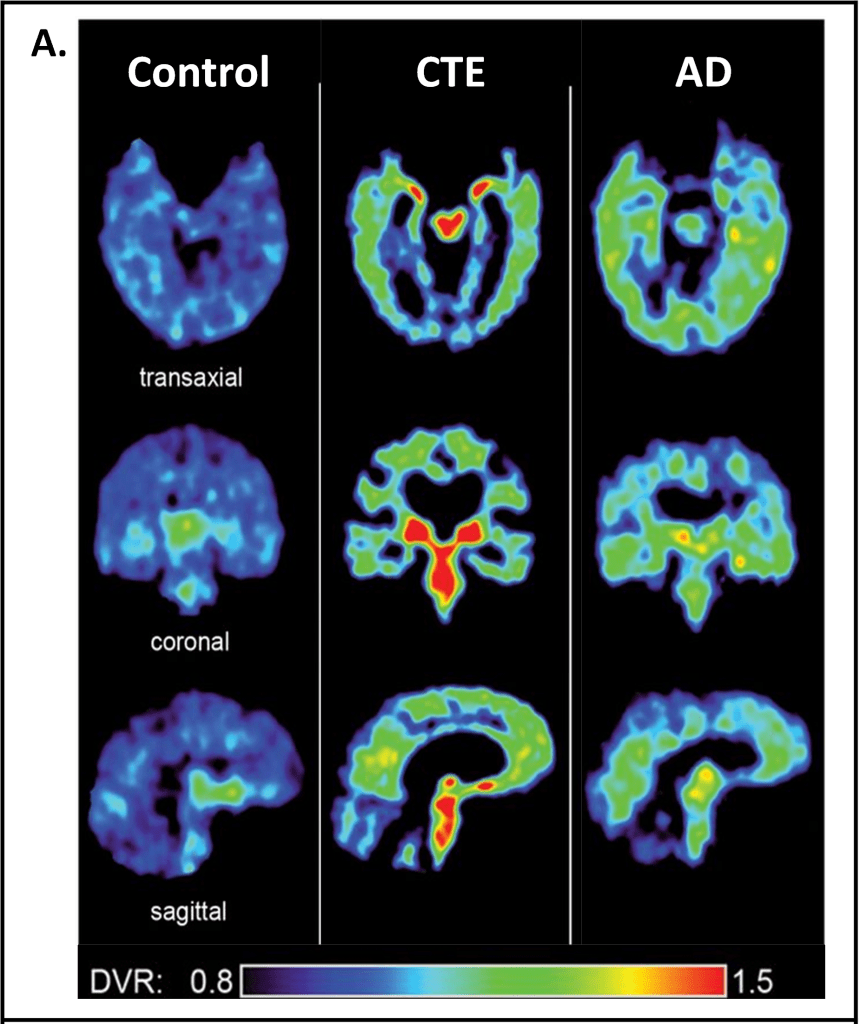

Chronic traumatic encephalopathy (CTE) is a disease linked to repetitive brain trauma and an accumulation of numerous mTBIs. CTE was first identified postmortem in American football players but has since been diagnosed postmortem in amateur athletes as well. CTE pathology involves phosphorylated tau proteins aggregating around blood vessels, astrocytes (glial cells that support neurons), and cortical gray matter in the brain3,4. Tau is a protein that stabilizes microtubules, which are cytoskeletal proteins that contribute to structural integrity and communication between neurons. When tau is overly phosphorylated (addition of a phosphate group to the molecule causing changes to its function), it no longer binds to microtubules in the neurons, leading to the destabilization and eventual death of neurons5. Phosphorylated tau is implicated in other brain diseases like Alzheimer’s disease and is hypothesized to be a cause of neurodegeneration. Interestingly, the pattern of phosphorylated tau observed in CTE is distinct from that of Alzheimer’s disease, suggesting that CTE has a different etiology (Fig. 2)6. CTE is associated with a range of symptoms, the most common being extreme changes in mood (depression and hopelessness), behavior (extreme impulsiveness and physical/verbal violence), cognitive decline, and impaired motor abilities like gait7.